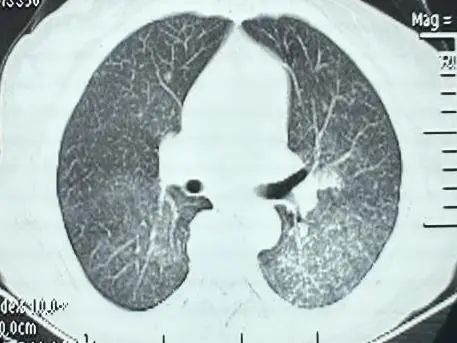

图片

2024-5-2胸部CT影像